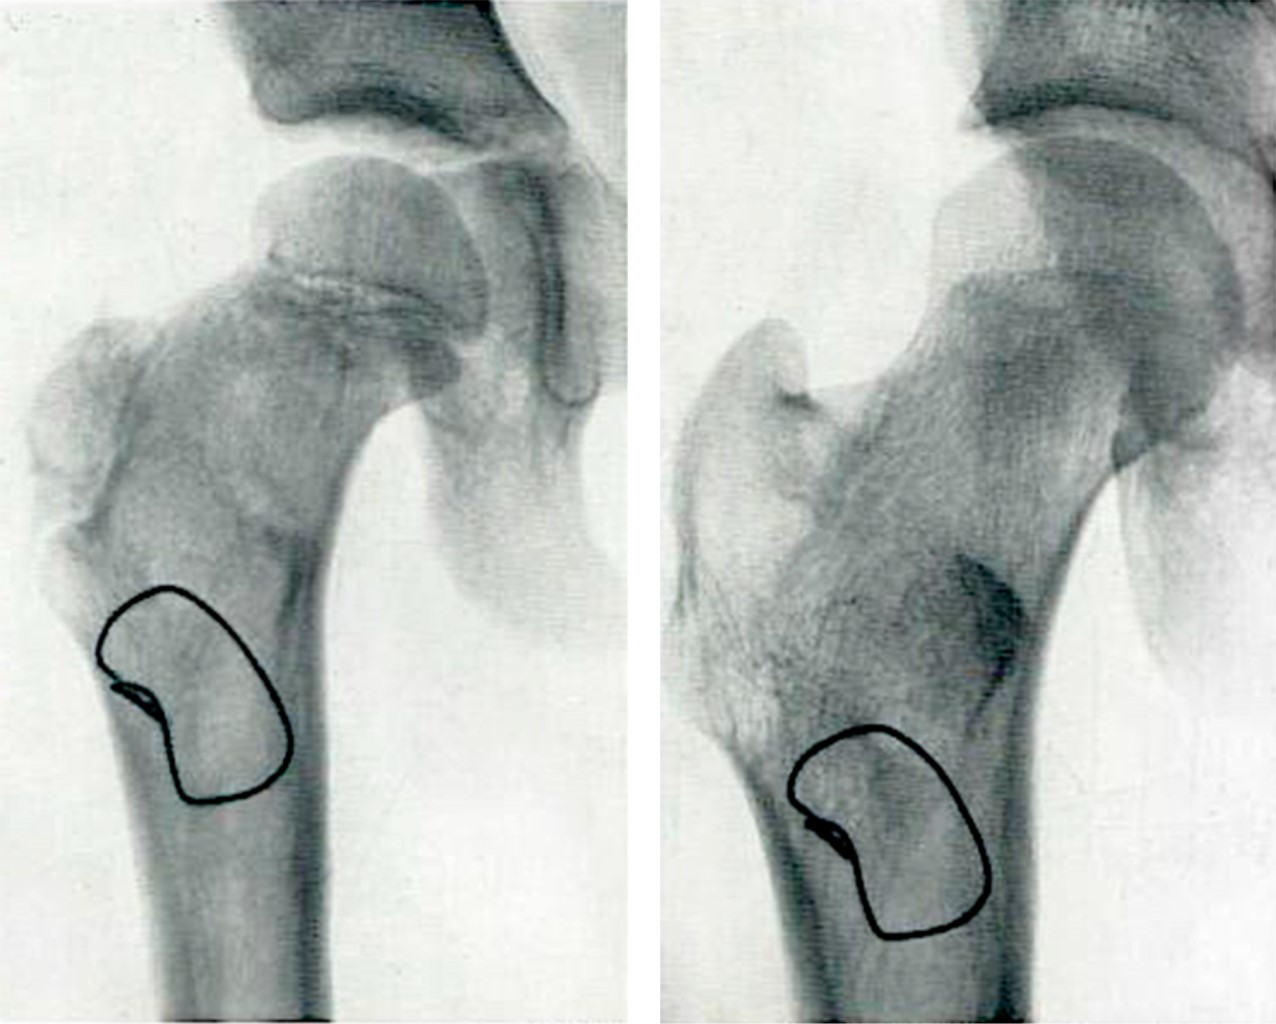

El siguiente hito ocurrió en 1943, cuando Moore y Bohlman,42 trabajando en Austenal Labs (que se convertiría más tarde en Howmedica), diseñan una prótesis que invade el espacio intramedular metadiafisiario con vástagos formales (no sólo con "espigas"), con el fin de mejorar la estabilidad del implante. Hasta antes de esta propuesta, ninguna prótesis invadía el espacio intramedular con el concepto de estos autores. La prótesis de Moore (Figura 12A) fue modificada por el mismo autor y el diseño final cuenta con perforaciones a nivel de su tercio proximal para facilitar la fijación por crecimiento óseo por invasión en esos sitios.43 Casi al mismo tiempo Fred Thompson44 e Irwing S. Leinbach45 presentan otros modelos de hemiprótesis no cementada con invasión endóstica del fémur (Figura 12B y C).

De manera simultánea a la introducción de las hemiprótesis con vástagos que invaden francamente el endostio metadiafisiario, se desarrollan las primeras prótesis "ultracortas" que tienen un vástago que sólo invade el cuello y parte de la metáfisis proximal. Los argumentos para utilizar estos diseños fue que por experiencia clínica acumulada con las copas de recubrimiento tipo Smith-Petersen, se sabía que con estas copas no se obtenía una estabilidad satisfactoria, por lo que se diseñaron estos implantes ultracortos con la esperanza de que con un vástago intraóseo cérvico-metafisario se pudiera obtener una mejor estabilidad. Así, en 1950 los hermanos Robert y Jean Judet35 proponen el diseño de prótesis con "vástagos ultracortos". Estas prótesis fueron fabricadas en un inicio con vidrio y posteriormente con el plástico acrílico (Plexiglas®) (Figura 13A y B). Poco tiempo después otros autores, incluyendo a Thompson, diseñan modelos similares fabricados con Vitalium® (Figuras 13C y 14).